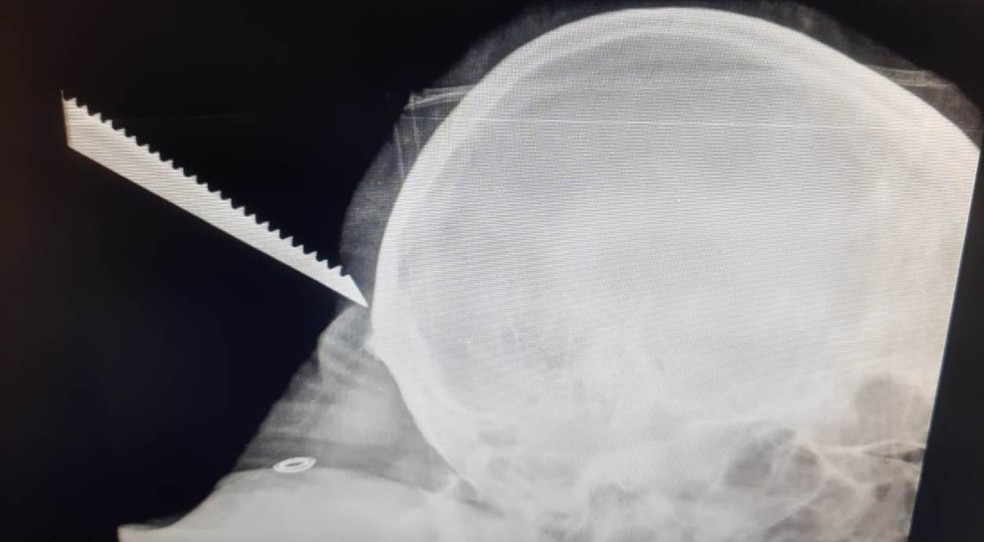

Um homem de 39 anos foi socorrido após ter a nuca perfurada por uma serra na região do bairro Dona Catarina, em Mairinque (SP), nesta quarta-feira (8).

No raio-x, a equipe médica constatou que não houve contato ou danificação da área do crânio. Segundo a prefeitura, a vítima não corre risco de morte.